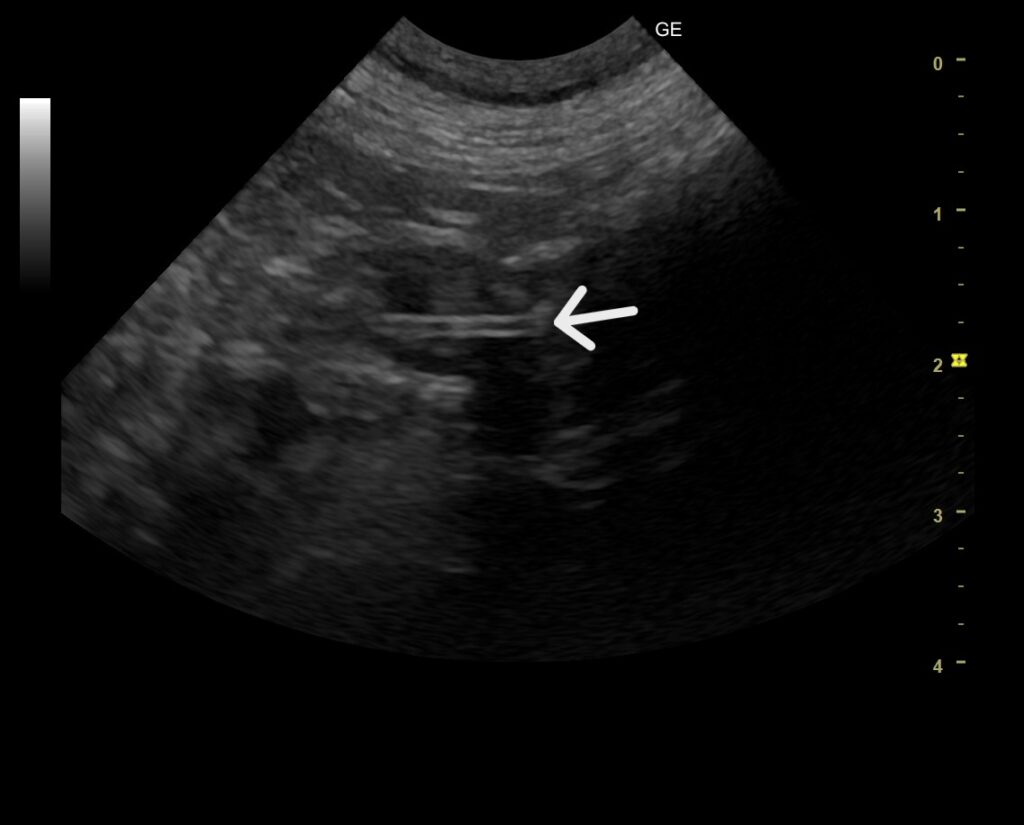

来院時のレントゲン検査ではひも状異物に特有なつづれ陰影などは認められませんでしたが、超音波検査で胃の出口にシャドーを引く丸い異物陰影と十二指腸へ続く線状の異物陰影を認めました。

幸いなことに、この時点で超音波検査でも腸の綴れはありませんでしたが、飼い主様には内視鏡で腸に流れた紐を摘出できなければ開腹手術になることをお伝えしてお預かりしました。